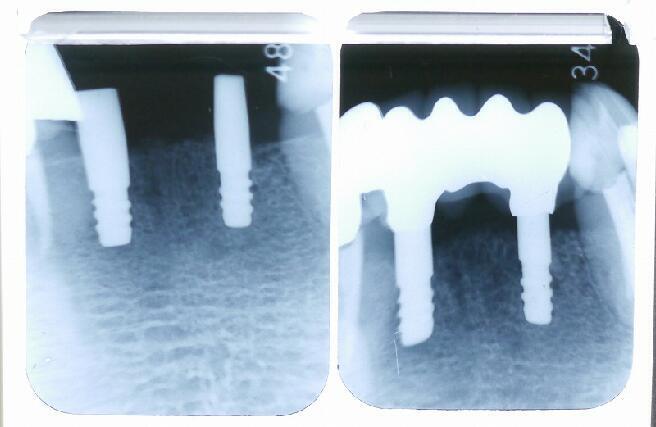

写真左は7月26日、埋入オペ直後で、写真右は10月5日、かぶせ物をして完成です